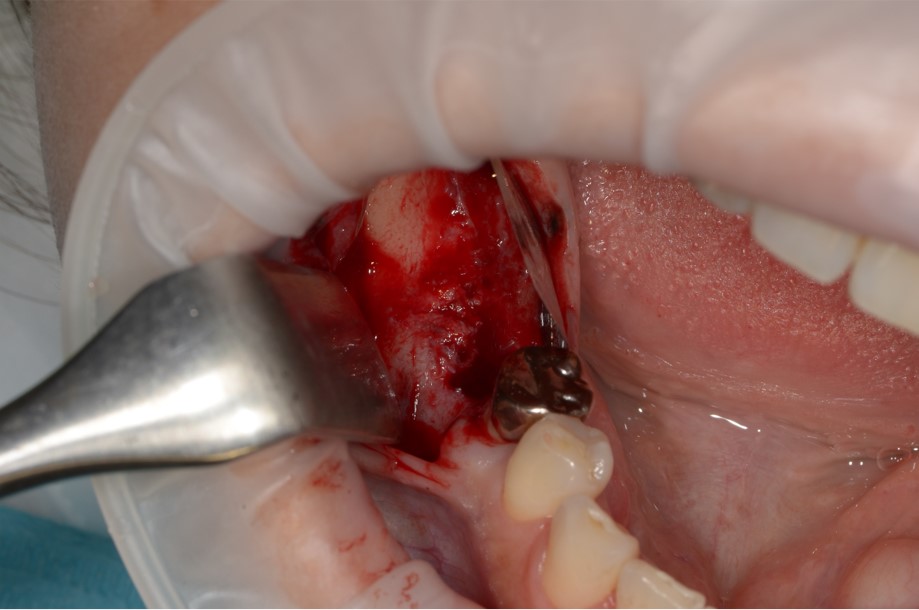

インプラント埋入のために、上顎の奥歯の骨の厚みが足りない場合に骨を作る処置です。もともとの骨の厚みにより、ソケットリフトもしくはサイナスリフトを選択します。骨を作る程度により治療内容や期間はさまざまです。

上顎の骨を持ち上げて同時にインプラントを埋入しました。